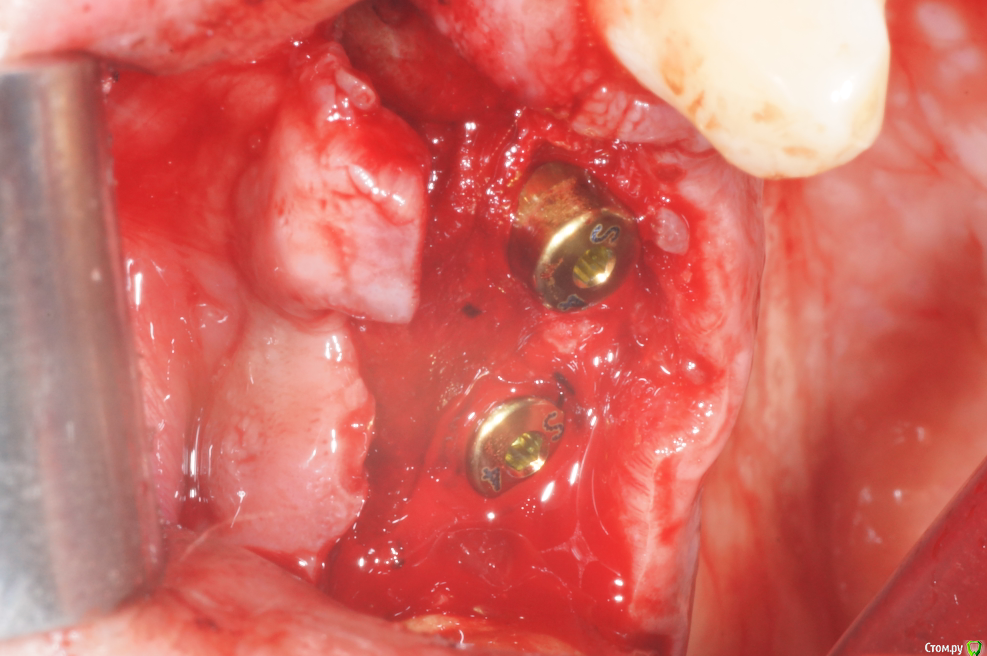

В начале планировал три имплантата, между зубами - 18,5 мм, в притык. Когда делал анестезию посмотрел наконец-то в рот (не смейтесь, внимательно посмотрел) - подумал, что моляр и два премоляра ортопед может не всунуть. Короче, передумал и решил ставить два и если че - пусть мостик или консоль делает.

Это я косанул. Хотел ровнехонько в 1.4 а вышло немного дистальнее. Ортопед, правда, уже одобрил, я немного волновался в первые дни.